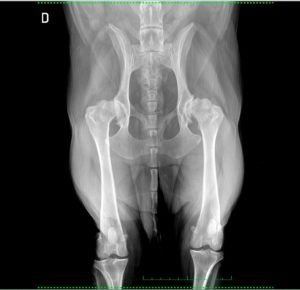

• Ecografías: abdominal, torácica, cervical, tejido superficial, intervencionista.

• ⁠Radiodiagnóstico: informes radiológicos (radiografías y TAC).

Envíanos un e-mail con la historia clínica completa del paciente, junto al estudio en formato DICOM y recibirás un informe detallado en 48-72H. ¡Consúltanos!